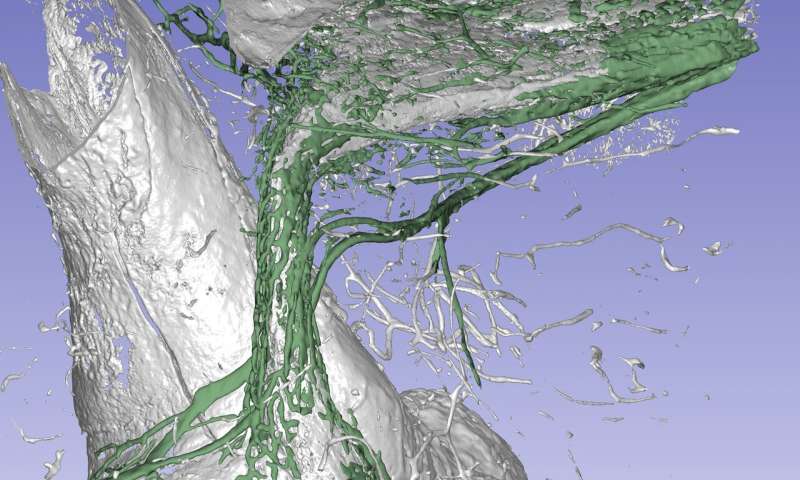

Immagine: una radiografia di sincrotrone dell’organo dell’equilibrio dell’orecchio interno umano mostra un canale a forma di rene con un diametro di appena ca. 0,5 mm. L’orecchio interno è stato ricostruito tridimensionalmente in un programma per computer e l’osso circostante è stato reso trasparente. Si pensa che i vasi di colore verde che circondano il canale assorbano e puliscano il fluido nell’orecchio interno. Si ritiene che l’interruzione di questa funzione possa causare la malattia di Ménière. Credito: Nordström et al.

L’organo dell’ equilibrio nell’orecchio interno è circondato dall’osso più duro del corpo. Usando i raggi X con sincrotrone, i ricercatori dell’Università di Uppsala hanno scoperto un sistema di drenaggio che si presume possa svolgere un ruolo importante nell’insorgenza della malattia di Ménière, un disturbo comune e problematico.